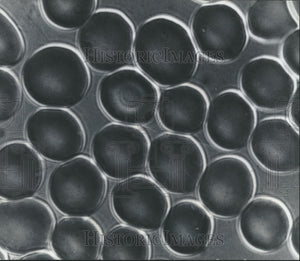

Image caption appears here